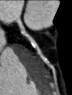

These scans use X-rays and generate detailed pictures of the heart arteries.

A scan can identify narrowings before any harm or disease, such as heart attack or angina happen.